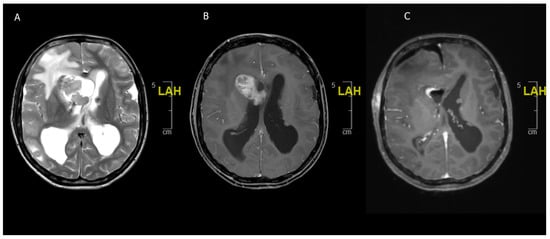

Figure 3. An 11-year-old boy presenting with headaches and blurry vision. (A) Preoperative MRI scan showing a 6.1 × 4.0 × 3.4 cm T2 hyperintense and contrast enhancing (not shown) lesion suggestive of (non-NF) optic pathway glioma. (B) Postoperative MRI scan after partial resection with tumor rest in the optic pathway. Histology confirmed a BRAF600 mutated pilocytic astrocytoma. (C) Follow-up MRI scan after 4 weeks of MEK inhibitor treatment showing a nearly complete regression of the tumor.

Most pLGGs, even if they do not include one of the typical driver mutations, contain mutations affecting the MAP-Kinase pathway. This could make them possible targets for BRAF/MEK inhibitor therapy [64,76]. The two best-known BRAF/MEK inhibitors currently being investigated in pLGG are selumetinib and trametinib, with skin toxicity being the most frequently described adverse event of the treatment [74,78,82,83] (Figure 3).

PLGGs harboring KIAA1549-BRAF mutations are more responsive to BRAF inhibitors than BRAFV600E-mutated tumors [77]. A recent phase II trial for recurrent or progressive pLGG showed that patients treated with selumetinib had a two-year PFS of 78 ± 8.5% and that visual fields and acuity improved or remained stable in the majority of patients, concluding that selumetinib leads to prolonged disease stability [78]. A current prospective trial investigating trametinib in pLGG is ongoing; the results are yet to be published (NCT02124772). In two retrospective cohort studies with a total of 28 patients, 12 patients showed a minor or partial response, while 16 patients achieved stable disease when treated with trametinib [82,83]. In one of the studies, around a third showed disease progression over the course of treatment, while in the other cohort, all the patients achieved disease control [82,83]. There is currently a trial ongoing comparing MEK/BRAF inhibitors to a CV regimen in pLGG, focusing on overall response rate (ORR), PFS, and OS; the results are yet to be published (NCT02684058). Some studies have observed a paradoxical activation of tumor growth with BRAF/MEK inhibitor treatment, especially in KIAA1549-BRAF- and NF-1-mutated pLGG [64,84]. This might prompt even more specific therapies for the distinct mutations [84]. Another challenge after the successful initiation of BRAF/MEK inhibitors is to decide when to discontinue treatment, weighing the risk for tumor recurrence and treatment side effects against each other. Tumor progression is often observed after the termination of BRAF/MEK inhibitors [82,83]. Target therapy trials for LGG are currently only carried out within the pediatric population.